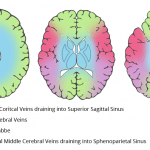

- Hyperattenuating appearance of the superior sagittal sinus, straight sinus, bilateral tentorial and cortical veins, both transverse sinuses, and the confluence of sinuses

- Dural venous sinus thrombosis

Findings concerning for thrombosis of the superior sagittal sinus, straight sinus, bilateral tentorial and cortical veins, both transverse sinuses, and the confluence of sinuses. Recommend brain MRI with and without contrast for further evaluation.